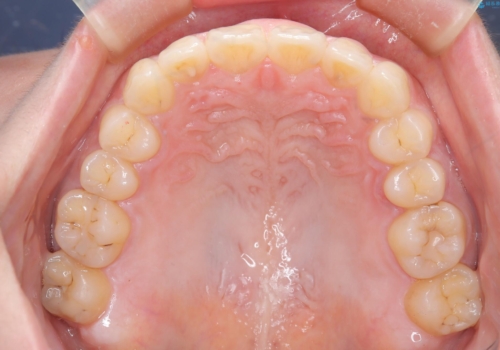

- 口元の突出感、歯のがたつきを主訴に来院された患者様です。非抜歯にて口元を下げるような治療計画を立案しました。非常に治療に対して真面目で協力的な患者様で、一緒に理想形を相談しながら治療を進めました。矯正前には、虫歯治療や親知らず抜歯を行っています。噛みしめ癖が強く、終盤は奥歯の噛み合わせのためにゴム掛けにご協力いただきました。